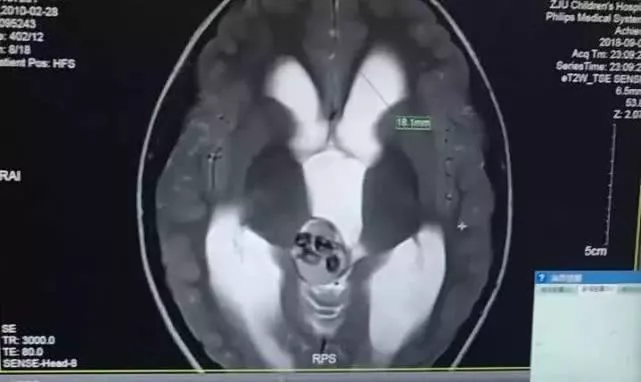

Bác sĩ Thẩm đã kiểm tra CT của Tiểu Cương, kết hợp với các triệu chứng trước đây như đau đầu, nôn ói… bác sĩ đã cho Tiểu Cương làm kiểm tra MRI để đưa ra chẩn đoán chính xác. Cuộc kiểm tra phát hiện rằng, dịch tích trong não của Tiểu Cương càng ngày càng nhiều, chiều rộng não thất của đứa trẻ 5 tuổi bình thường khoảng 3cm, nhưng của Tiểu Cương đạt đến 18cm.

Những vật chất dạng viên ở trong não Tiểu Cương chính là những chiếc răng và có tổng cộng tới 9 chiếc

Điều kỳ lạ là, khối lượng trong trung tâm hộp sọ là một vật liệu dạng hạt, mật độ vô cùng cao. Theo kết quả kiểm tra, bác sĩ Thẩm phán đoán khối cục trong đầu của Tiểu Cương có thể là thứ mang tính chất xương. Sau khi đánh giá, bác sĩ quyết định phẫu thuật cho Tiểu Cương.

Ca phẫu thuật của Tiểu Cương diễn ra tại Bệnh viện Nhi Chiết Giang, được tiến hành bởi bác sĩ Thẩm Chí Bằng. Trong quá trình phẫu thuật, bác sĩ sửng sốt phát hiện những vật chất dạng viên ở trong não Tiểu Cương chính là những chiếc răng và có tổng cộng tới 9 chiếc. Ngoài ra, còn có một lượng tóc nhỏ, vỏ não, xương và một số chất khác.